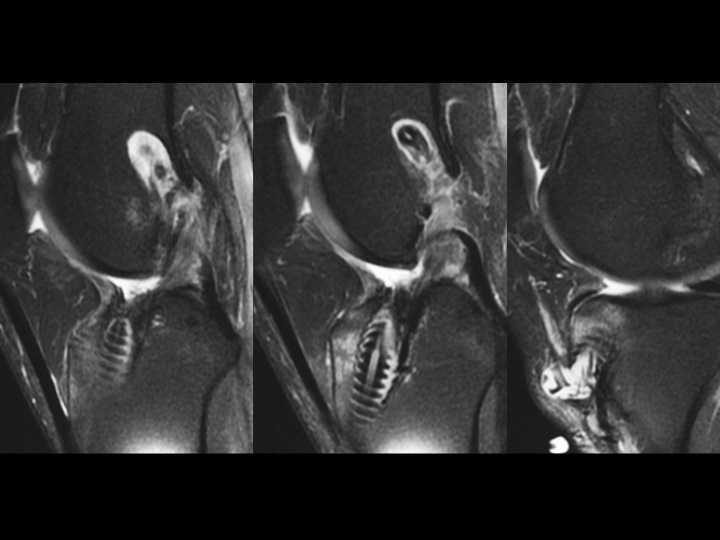

Figure 4 for case ACL graft device ( RID5523 )

Figure 4

There is fragmentation of one of the 2 bioabsorbable interference screws in the tibial tunnel, with a fragment situation in a cyst superficial to the tibial tunnel. The ACL graft is markedly attenuated. The last slide shows the failed, fragmented bioabsorbable femoral crosspin (arrow) from the initial reconstruction in 2011. Might be time for a Bone-Patellar Tendon-Bone autograft with metallic fixation?